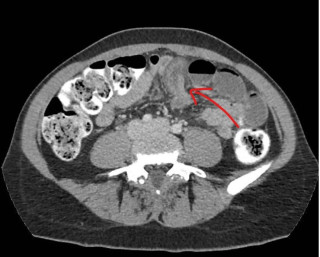

Case presentation

A 45-year-old man with no relevant past medical history presented with acute diffuse abdominal pain following a forceful sneezing episode. Physical examination revealed localized right-sided abdominal tenderness without peritoneal signs. Laboratory tests showed mild leukocytosis with normal inflammatory markers and hemoglobin. Contrast-enhanced computed tomography demonstrated a mesenteric hematoma associated with moderate hemoperitoneum and focal mural hypoenhancement of an ileal loop, without active arterial extravasation (Figure 1). Urgent surgical exploration revealed approximately 500 mL of hemoperitoneum, a large mesenteric hematoma, and an adjacent intestinal pseudodiverticulum (Figures 2-3). Segmental small bowel resection including the diverticulum was performed. Histopathological analysis confirmed fresh mesenteric hemorrhage and pseudodiverticular changes without evidence of malignancy, vasculitis, or vascular malformation. The postoperative course was uneventful, and the patient remained asymptomatic at six-week follow-up.